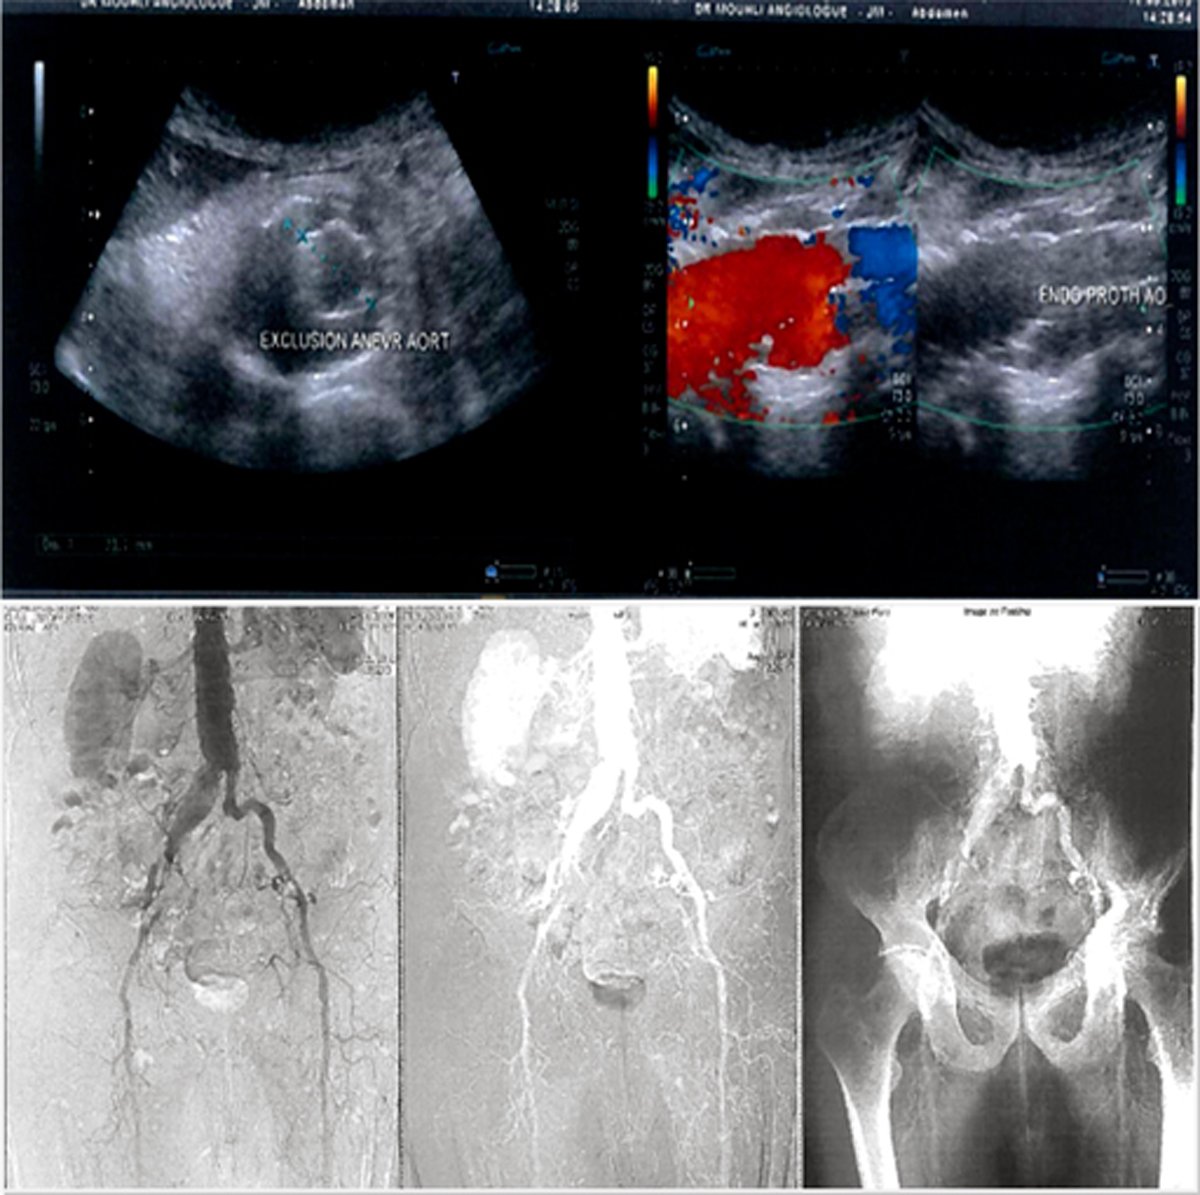

Monsieur X née le1925, sous oxygéne, 2litres en continu pour emphséme pulmonaire ,repercussion cardiaque droite avec hypertrophie ventriculaire droite, la coronographie est normal pour son age,qui présentait un anévrisme de l’aorte abdominale qui est à 45 mm.avec thrombus murale et un chenal circulant Par contre, il existe un anévrisme iliaque sans aucun collet relié à l 1anévrisme de l 1aorte abdominale à 39 mm. Devant le tableau d 1un anévrisme énorme de l 1artère iliaque primitive sans collet, on est obligé de réaliser la mise en place d 1une endoprothèse aortique vu que l 1artère iliaque gauche est extrêmement athéromateuse et difficile d1accès, on décide de réaliser la mise en place d 1une endoprothèse aorto uni iliaque droite avec mise en place d 1un occluder à gauche associés à un pontage croisé droit 1 gauche.

Patient présentant un anévrisme de l’aorte abdominale qui est à 45 mm. Par contre, il existe un anévrisme iliaque sans aucun collet relié à l’anévrisme de l’aorte abdominale à 39 mm. Devant le tableau d’un anévrisme énorme de l’artère iliaque primitive sans collet, on est obligé de réaliser la mise en place d’une endoprothèse aortique vu que l’artère iliaque gauche est extrêmement athéromateuse et difficile d’accès, on décide de réaliser la mise en place d’une endoprothèse aorto uni iliaque droite avec mise en place d’un occluder à gauche associés à un pontage croisé droit / gauche.

En conclusion : Mise en place d’une endoprothèse aorto-uni-iliaque pour anévrisme de l’aorte abdominale et surtout anévrisme iliaque de 39 mm avec la réalisation d’un pontage croisé droit / gauche ainsi qu’une thrombo-endartériectomie ilio-fémorale bilatérale.